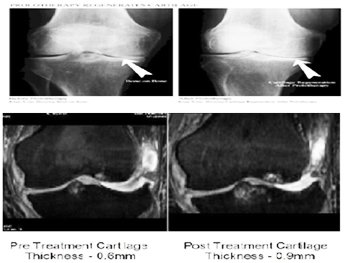

About 75- 85% of patients receiving the treatment experience significant improvement, with reduced pain and improved joint function. EMRT does not provide instant relief or instant re-generation. It’s a progressive medical therapy where the growth of cartilage may progress until 9-10 months’ post therapy. H200, H50 and PERSONAL COMPACT DEVICES has limitations in treating few disorders.